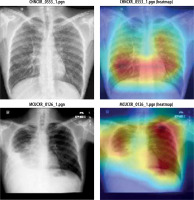

Figure 11 shows heatmap for segmented images indicating presence of disease infected regions.